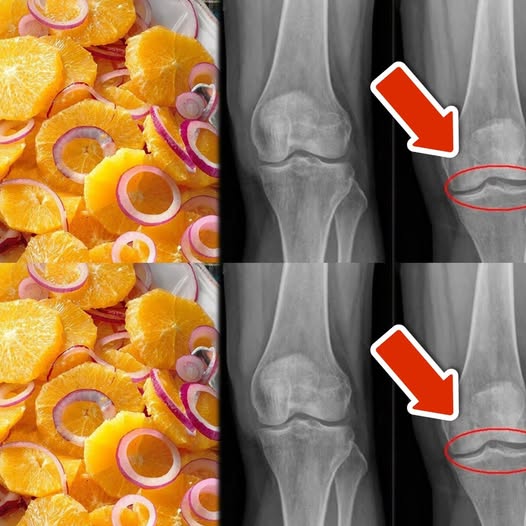

Wprowadzenie: Zdrowe kolana, chrząstki i więzadła to podstawa codziennej mobilności i komfortu. Wiele osób szuka naturalnych sposobów na wzmocnienie stawów i redukcję bólu, a…